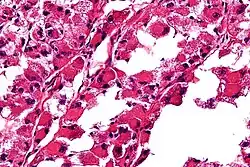

Micrograph of an alveolar soft part sarcoma, showing the characteristic alveolar-like architecture and cells with eccentric nuclei and abundant eosinophilic cytoplasm. H&E stain.

• The term alveolar comes from the microscopic pattern, visible during the analysis of slides of ASPS under the microscope in histopathology. The tumor cells seem to be arranged in the same pattern as the cells of the small air sacks (alveoli) in the lungs. However, this is just a structural similarity. ASPS was first described and characterized in 1952.[1]

The definitive diagnosis of ASPS is based on its appearance under the microscope (i.e., its histomorphology), and presence of the characteristic chromosomal translocation (i.e., cytogenetics).

ASPS' histomorphologic features include an alveolar-like pattern at low magnification and the presence of large cells with abundant eosinophilic cytoplasm and eccentric nuclei. Calcifications are commonly present, as may be seen with slow-growing neoplasms.